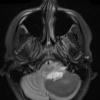

NEOPLASMS (GLIAL)

Astrocytoma, pilocytic - Microscopic (12)